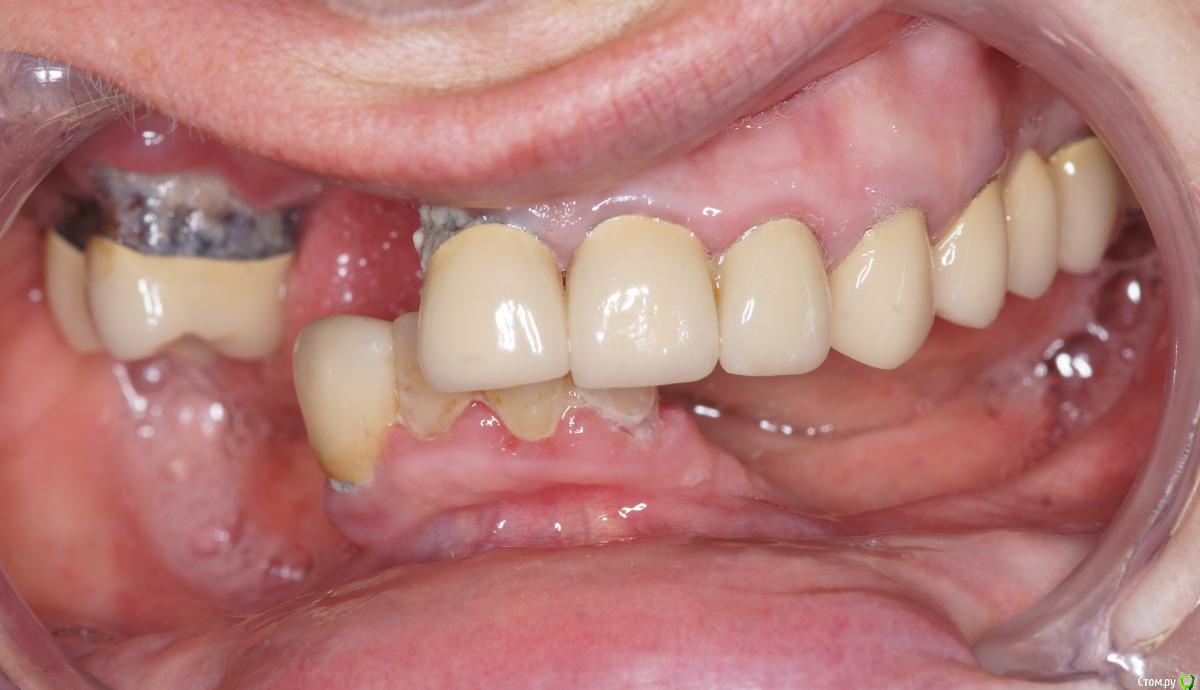

Dman Опубликовано 13 марта, 2019 Поделиться Опубликовано 13 марта, 2019 (изменено) Обратилась пациентка, панорама 2012 панорама 2018 Сейчас по ощущениям еще хуже Если с низом более или менее понятно, 4 винта и балка, чтобы разгрузить кость, то сверху вообще непонятно. Желание пациента жить и жевать. За эти 7 лет поменяли 7 съемных протезов, все они ей натирали и плохо держались. Анамнез чист, принимает только эстрогены Если есть кто-то из тольятти, кто готов взять пациента, с удовольствием передам контакты. Изменено 13 марта, 2019 пользователем Dman Ссылка на комментарий

колесников Опубликовано 13 марта, 2019 Поделиться Опубликовано 13 марта, 2019 Мне больше не нравится область 14-12. Чтобы сделать там красиво ,надо сильно постараться. И не раз. Ссылка на комментарий

АнтонТЛТ Опубликовано 13 марта, 2019 Поделиться Опубликовано 13 марта, 2019 Оценить зубы слева, удалить все зубы справа, через 2-3 мес аугментация с жёстким каркасом, через 6-8 мес имплантация 11,13,14,16, ещё через 4-6 мес фдм с восстановлением прикрепленных тканей, потом временное протезирование. Затем постоянное мостами 11-13 и 14-16. Ссылка на комментарий